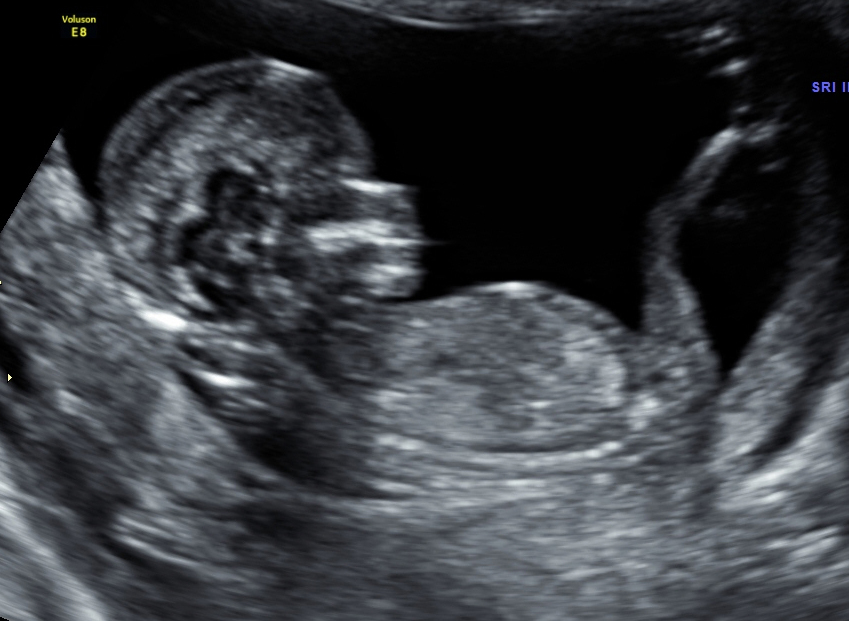

I had an ultrasound today and the doctor told me that my baby could be a girl, because she couldnīt see a penis. And then she saw 3 white dots...Everything is still very little and unsharp so she didntīt want to say "100%"

So do you girls moms think itīs a girl? Did it look like that with your girls?